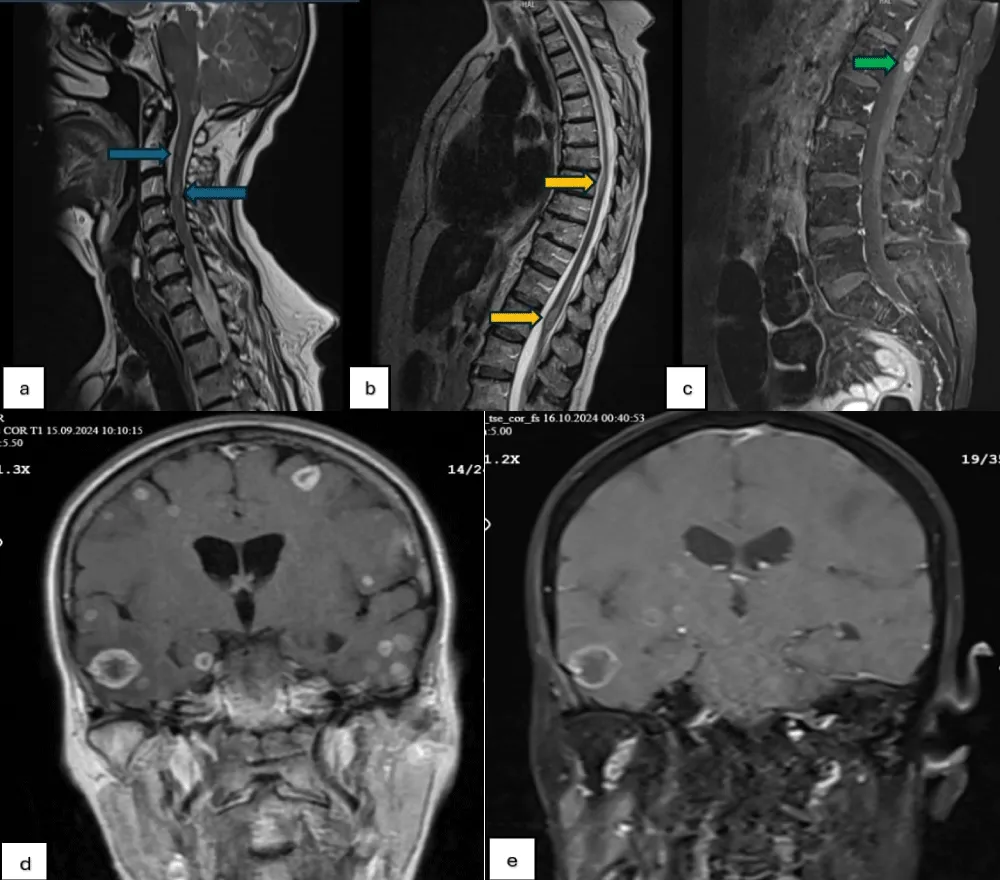

The diagnosis of LM is primarily made after a comprehensive history and physical examination, followed by brain and cervical-thoracic-lumbar spinal MRI, and cerebrospinal fluid (CSF) analysis. Diffuse and focal contrast enhancement on T1-weighted contrast-enhanced MRI is the typical appearance and is the primary diagnostic tool for LM [3,6]. As in the case presented here, a non-enhancing mass may also appear on T1-weighted images. Contrast-enhanced FLAIR sequences are more sensitive in detecting LM in these cases [3]. Contrast enhancement on MRI is seen in both LM and inflammatory meningitis. CSF sampling should be used to differentiate [7]. A lumbar puncture was not performed in our case due to the short expected survival time and the risk of herniation of the space-occupying lesion in the brain as a result of the lumbar puncture (Figure 1).

Figure 1: (a-c) Dural metastases with nodular enhancement along the spinal cord on T1- and T2-weighted MRIs, (d): Extensive metastases in the brain on pre-RT T1-weighted MRI, (e) Extensive metastases in the brain on post-RT T1-weighted MRI.

Differential diagnosis should include meningitis or encephalitis caused by various organisms, primary brain lesions, autoimmune and vascular diseases, and paraneoplastic syndromes [4]. In our case, the eosinophil count was 100 cells/mcL, thus ruling out a diagnosis of parasitic infection. The patient’s lack of a history of tuberculosis and normal vital signs also ruled out bacterial infections. Whole-brain RT should be the primary treatment option for patients who do not require urgent decompression and whose brain metastases are too extensive for surgical intervention. Various dose fractionations are accepted for WBRT. The two most commonly used treatment schedules are 30 Gy in 10 fractions or 20 Gy in 5 fractions. Shorter schedules of 10 Gy in a single fraction or 12 Gy in 2 fractions can also be applied [5]. In our patient, we approached whole-brain irradiation for a total of 14 Gy in 2 fractions. Radiotherapy for lesions around the spinal cord can be administered comprehensively as craniospinal or as involved field radiotherapy (IFRT) applied only to symptomatic areas [5]. However, it should be noted that leptomeningeal disease is a diffuse condition, and focal RT is a temporary solution [5]. Limited data are available on IFRT dose fractionation. According to previous studies, doses range from 20 to 40 Gy in 5-20 fractions. In our patient, 4 x 5 Gy RT was administered to the affected areas around the spinal cord.